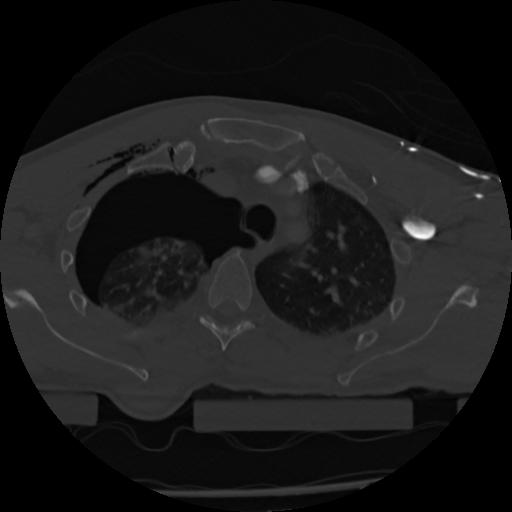

22 ANGIO,CE,Vol,0.5,ANGIO,,